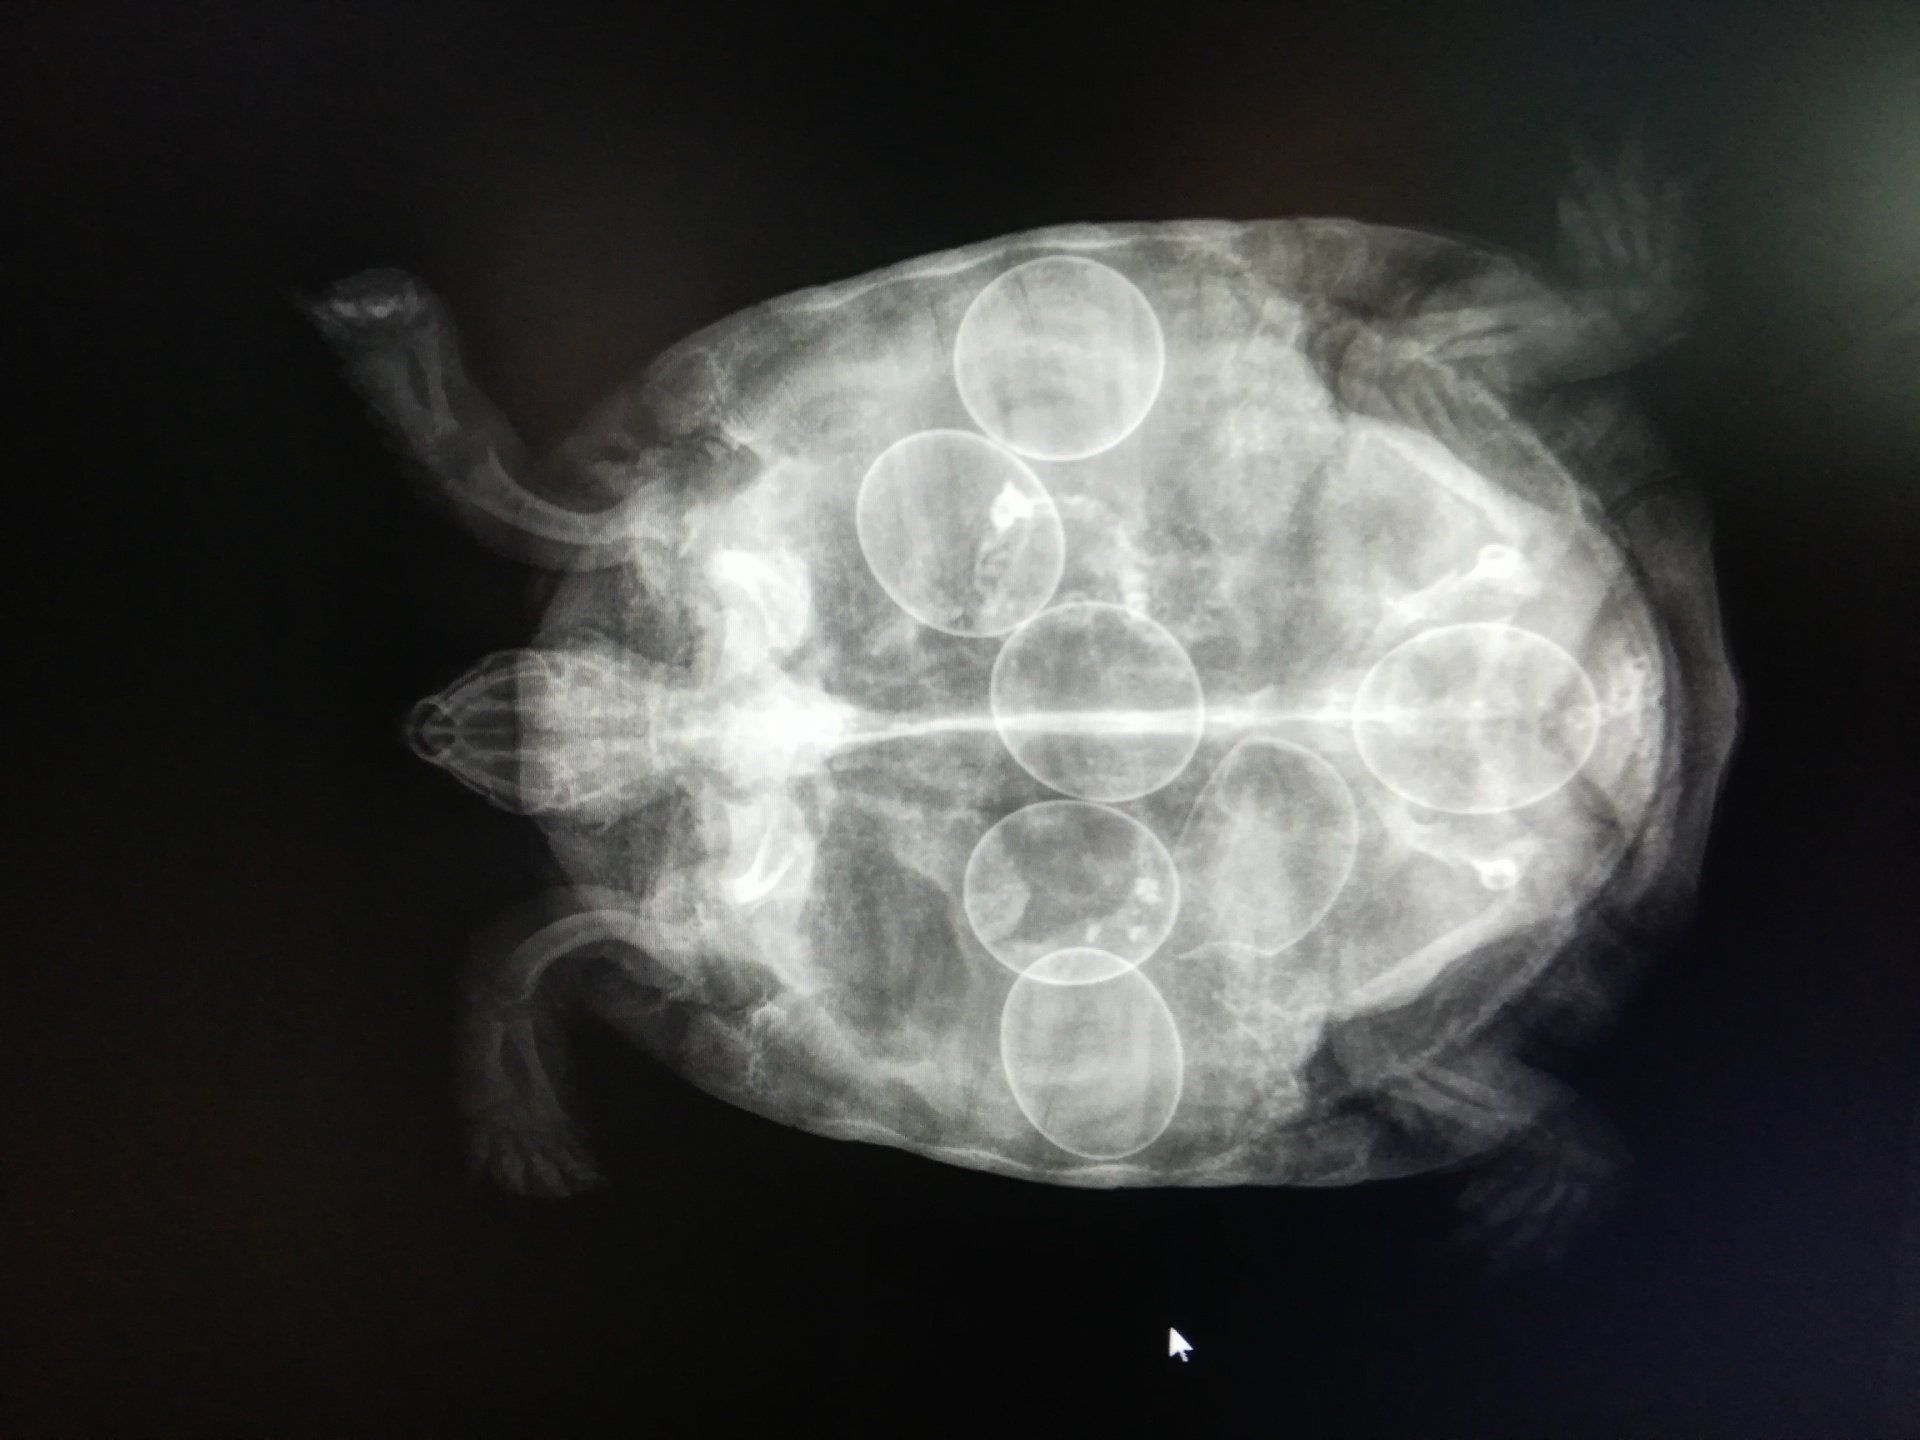

Abdominal X-ray:

For the search for pathologies concerning the abdominal organs (liver, kidneys, spleen, digestive system, etc.)